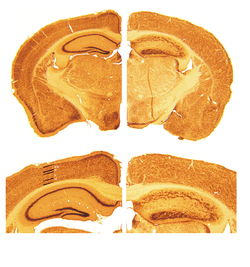

A reeler is a mouse mutant, so named because of its characteristic "reeling" gait. This is caused by profound hypoplasia of the mouse's cerebellum, in which the normal cerebellar folia are missing. The mutation is autosomal and recessive.

Cortical neurons are generated normally but are abnormally placed, resulting in disorganization of cortical laminar layers in the CNS. The reason is the lack of Reelin, an extracellular matrix glycoprotein, which during the corticogenesis is secreted mainly by the Cajal-Retzius cells. In the reeler neocortex, cortical plate neurons are aligned in a practically inverted fashion (‘‘outside-in’’). In the ventricular zone of the cortex fewer neurons have been found to have radial glial processes.[1] In the dentate gyrus of hippocampus, no characteristic radial glial scaffold is formed and no compact granule cell layer is established.[2] Therefore, the reeler mouse presents a good model in which to investigate the mechanisms of establishment of the precise neuronal network during development.

Key pathological findings in the Reeler brain structure

- Inversion of cortical layers.

- Dispersion of neurons within cortical layers.

- Decreased cerebellar size.

- Failure of preplate to split